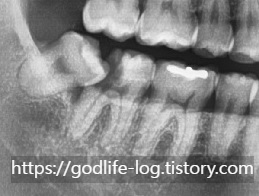

위 사진의 경우 사랑니 때문에 충치가 너무 심해져서 치아를 더 이상 살릴 수 없는 경우이고 발치가 필요한 상황입니다.

하지만 잇몸 뼈 자체는 다른 부분이랑 비슷하게 잘 유지되고 있기 때문에 사랑니와 충치가 심한 치아 함께 발치 후 바로 임플란트를 식립 할 수 있습니다.